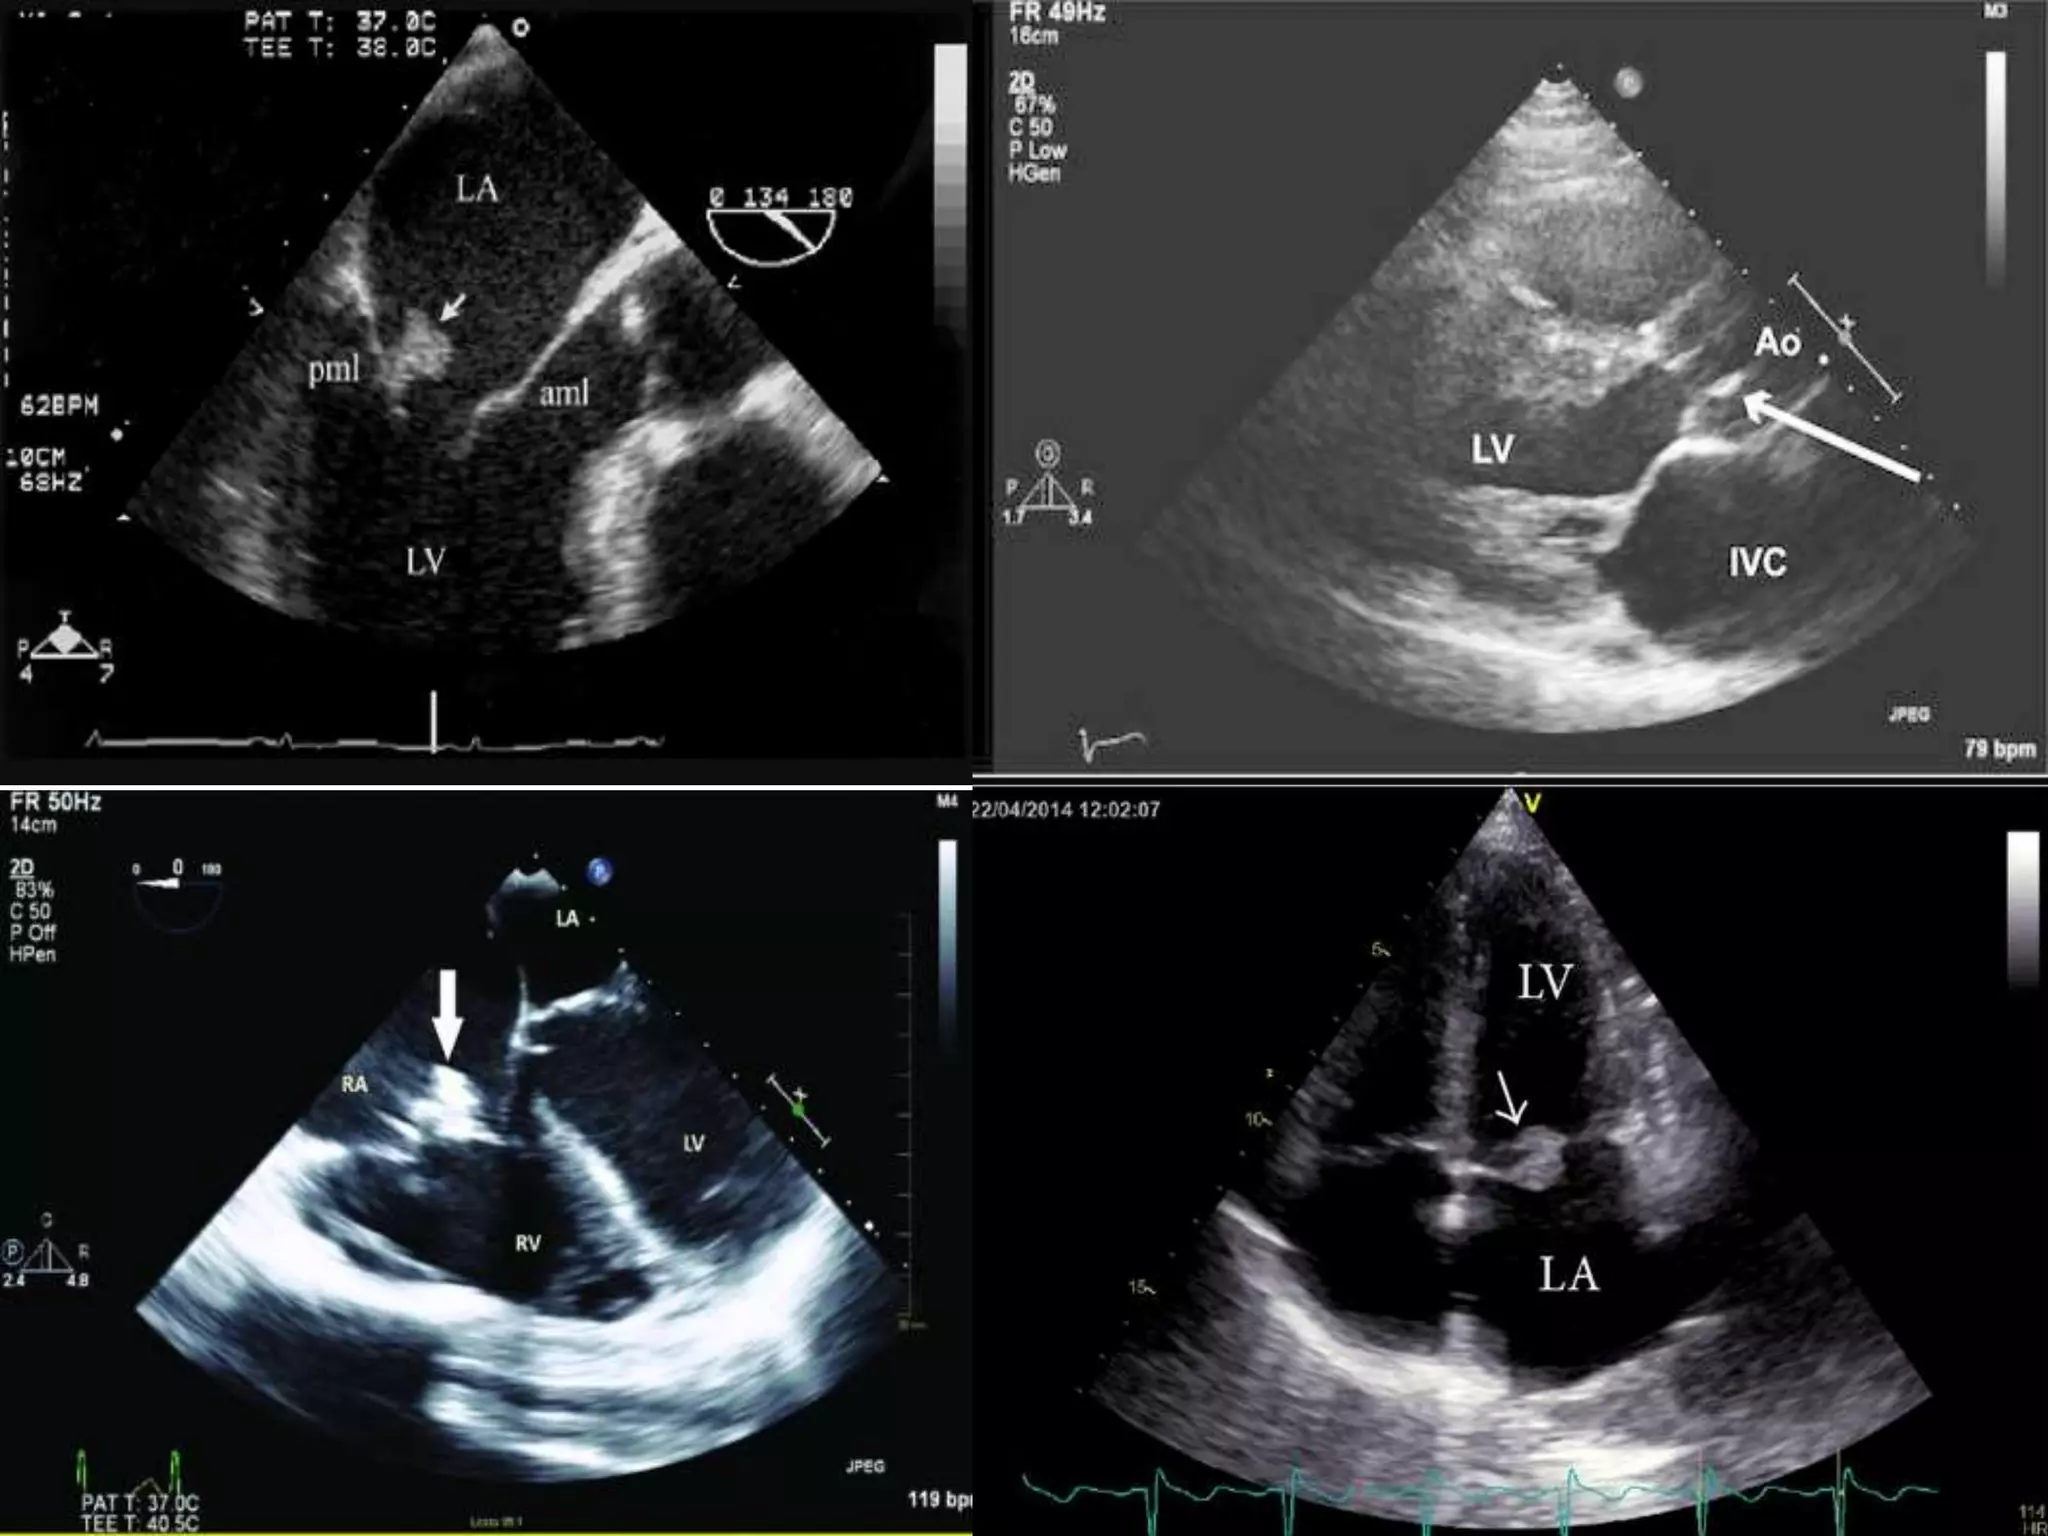

 As discussed, central to the diagnosis of IE being a part of major criteria,

echocardiography

 Hanging oscillating intra cardiac mass attached to valves, supporting structures,

implanted devices or in the path of regurgitant gets (ECHO)

 TTE vs TEE

 Cardiac CT – Strictly speaking, not indicated as per guidelines. Yet useful

 MRI brain

 As discussed,central to the diagnosis of IE being a part of major criteria, echocardiography  Hanging oscillating intra cardiac mass attached to valves, supporting structures, implanted devices or in the path of regurgitant gets (ECHO)  TTE vs TEE  Cardiac CT – Strictly speaking, not indicated as per guidelines. Yet useful  MRI brain